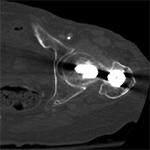

Complex cross-sectional geometry implants will result in streak artifact along the axes of greatest cross-sectional thickness (Buckwalter, 2011). In the presence of multiple implants the artifact will be most severe along the axis containing both implants. For example, with bilateral hip arthroplasties, the artifact will be most pronounced along the right-left axis as the beam travels through both implants (Figure 3). By orienting the hardware with shortest dimension of the implant perpendicular to the table, the amount of associated streak artifact will be reduced.

Artifact summation Artifact summation Windowing Windowing

Artifact Summation. (A) Scout image demonstrates bilateral total hip arthroplasties. (B) Axial CT image at the level of acetabular cup and femoral head shows severe transverse streaking related to total summed attenuation of metal components. Optimal Windowing. (A) Axial CT image of the pelvis viewed in soft tissue windows demonstrates extensive streak artifact due to total hip arthroplasty prohibiting evaluation of adjacent bone and soft tissue structure. (B) Same axial CT image set to bone windows results in improved visibility of adjacent bone and soft tissue anatomy.